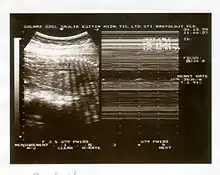

Image échographique d'une grossesse.

Il se réalise au cours d'une échographie, qui recherchera 5 critères (durant 30 minutes), un critère présent comptant pour 2 points (et 0 s'il est absent) :